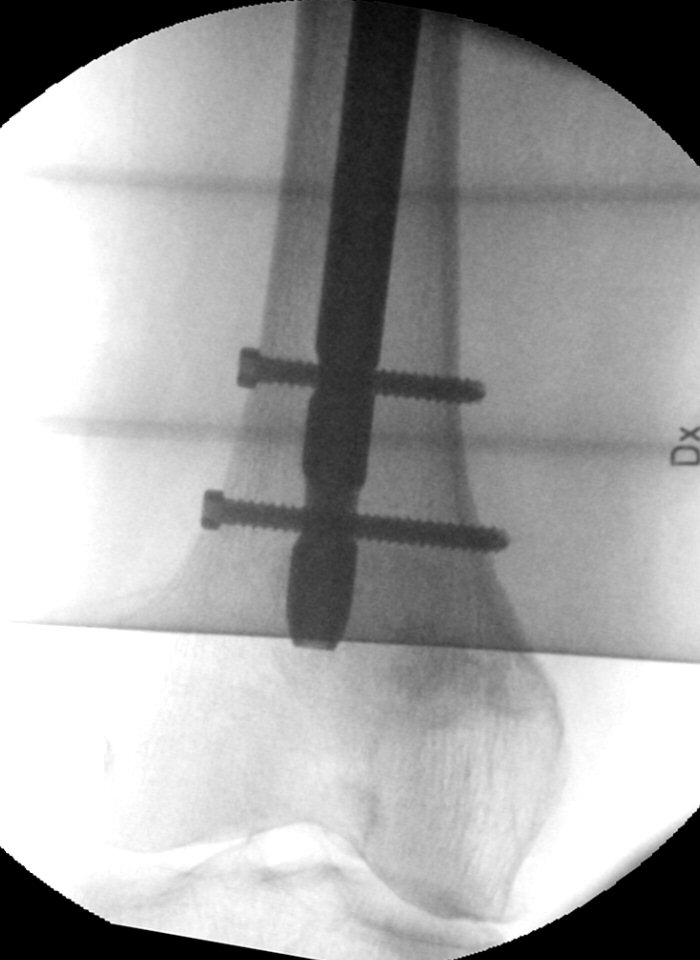

Knivspets markerar placering av statisk distal låsskruv. Notera att bilden är tagen exakt rakt från sidan.

- Gör hudsnitt

- För in pryl och kontrollera i både frontalvy och sidovy att spetsen är exakt mitt i hålet. Gör ordentligt märke.

- Borra i prylens hål, kontrollera i både frontal- och sidovy att du är mitt i hålet och med rätt vinkel.

- Mät med mätsticka hur långa skruvar som behövs.

- Skruva in skruvarna "lagom" hårt, se till i genomlysning att de hamnar rätt. Om de går alltför trögt, skruva ut och borra igen, låt borren “vandra runt” lite.

- Lagra peroperativa bilder om det inte är gjort tidigare.

Lagom lång gammaspik med bra läge på glidskruv, lagom långa låsskruvar varav en statisk och en dynamisk